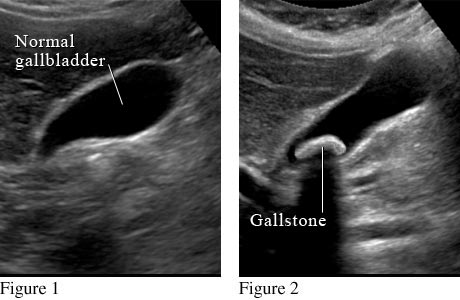

What a gallstone looks like on an abdominal ultrasound

Courtesy of Intermountain Medical Imaging, Boise, Idaho.

Figure 1 shows a normal gallbladder on ultrasound. Figure 2 shows a large gallstone in the gallbladder.